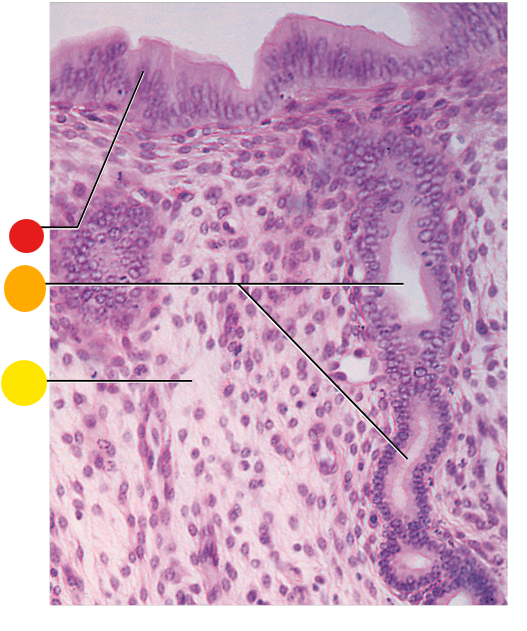

red

granulosa cells

orange

primary oocyte

what is this

primary follicle